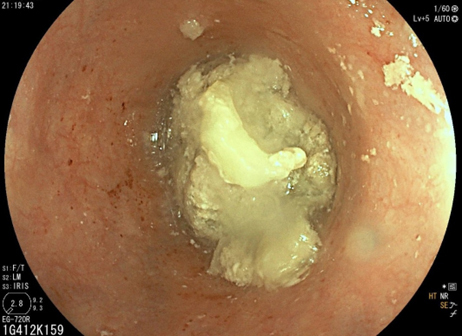

Les crampes épigastriques et la périodicité font partie du syndrome ulcéreux.

Cette symptomatologie épigastrique peut être le reflet d’une gastrite